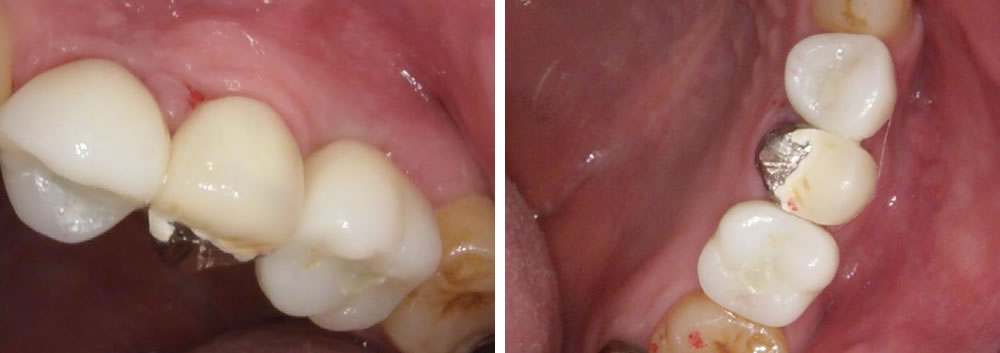

結果、しっかりと噛む事ができ、審美的にも回復する事ができました。